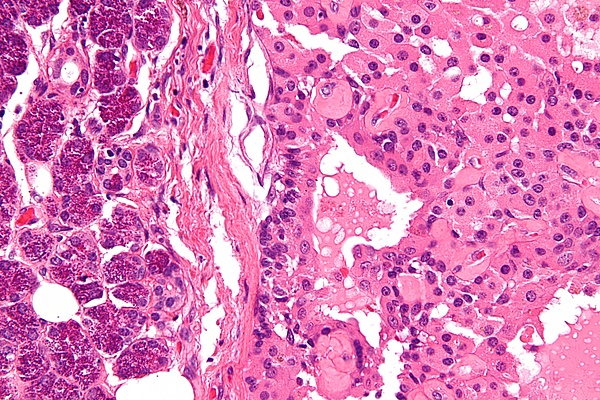

При исследовании под микроскопом онкоцитомы состоят из крупных розовых онкоцитарные клетки. Клетки называются онкоцитарными, потому что цитоплазма (тело клетки) заполнено тысячами митохондрий, типом клеточного механизма, который преобразует кислород в энергию. Онкоциты выглядят розовыми при исследовании под микроскопом, потому что митохондрии прилипают к эозину, красителю розового цвета, обнаруженному в гематоксилин-эозине . Опухоль можно охарактеризовать как хорошо очерченную, что означает наличие чёткой границы между опухолью и окружающей нормальной тканью слюнной железы.